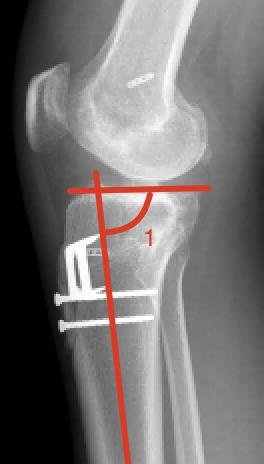

Slope

Het gewrichtsoppervlak van de knie heeft een hellingshoek tov het onderbeen (1), dit is de zogenaamde slope. Hoe groter de hoek, hoe groter de neiging van het femur om naar achter te schuiven tov het onderbeen (pijlen). Hoe groter, hoe meer kracht op de VKB. Deze hoek is duidelijk minder groot na de ingreep. En dus de krachten minder op de VKB.